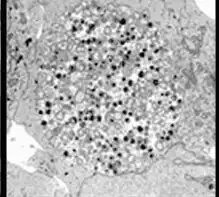

Chlamydia pneumoniae in HeLa cell 72 hours post infection

Chlamydia pneumoniae is a small gram-negative bacterium (0.2 to 1 μm) that undergoes several transformations during its life cycle. It exists as an elementary body (EB) between hosts. The EB is not biologically active, but is resistant to environmental stresses and can survive outside a host for a limited time. The EB travels from an infected person to the lungs of an uninfected person in small droplets and is responsible for infection. Once in the lungs, the EB is taken up by cells in a pouch called an endosome by a process called phagocytosis. However, the EB is not destroyed by fusion with lysosomes, as is typical for phagocytosed material. Instead, it transforms into a reticulate body (RB) and begins to replicate within the endosome. The reticulate bodies must use some of the host's cellular metabolism to complete its replication. The reticulate bodies then convert back to elementary bodies and are released back into the lung, often after causing the death of the host cell. The EBs are thereafter able to infect new cells, either in the same organism or in a new host. Thus, the lifecycle of C. pneumoniae is divided between the elementary body, which is able to infect new hosts but cannot replicate, and the reticulate body, which replicates but is not able to cause a new infection.[9]